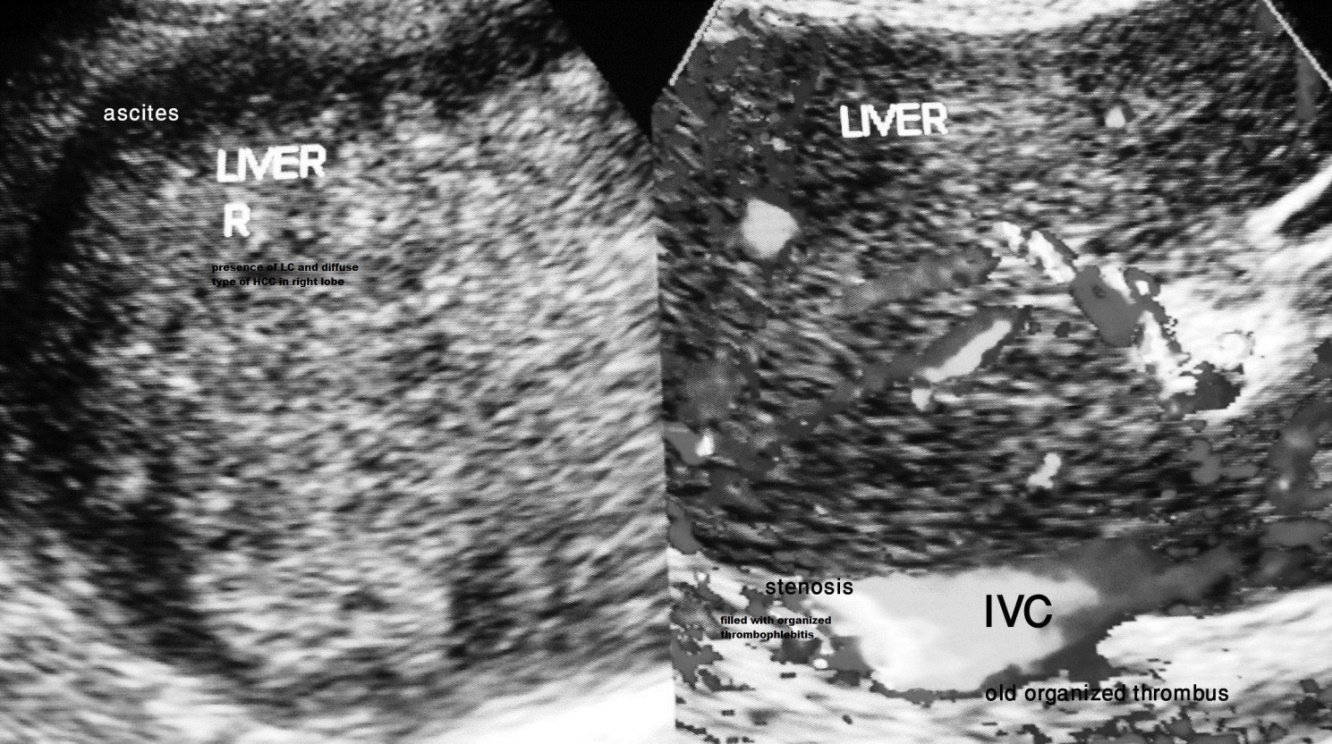

HVCS affects people of all age groups from infancy to old age. Its prevalence in a community is inversely related to the standard of hygienic and nutrition [30,41]. It is diagnosed by ultrasonography and color Doppler (US/CD) examination of IVC and the liver [42]. Common findings are localized stenosis of the IVC with thickened posterior wall at the site of hepatic vein opening, presence of old organized thrombophlebitis of different ages along the posterior wall of distal dilated segment often with evidence of hepatic venous outflow obstruction (Fig 1a & 1b) and abnormal blood flow pattern, biphasic or continuous instead of triphasic in IVC. HVCS has a long asymptomatic course with occasional acute exacerbation precipitated by bacterial infection marked by mild elevations of aminotransferases and/or bilirubin or ascites associated with neutrophil leukocytosis and elevation of levels of C-reactive protein and erythrocyte sedimentation rate. The disease is now managed by medical treatment [43].

Figure 1a. Hepatic Vena Cava Syndrome is diagnosed by ultrasonography and color Doppler examination of inferior vena cava & liver on detection of localized stenosis at the site of hepatic vein opening. Presence of acute exacerbation is indicated by occurrence hepatic venous outflow obstruction and past AE by presence of old organized thrombophlebitis along posterior wall of distal dilated segment of inferior vena cava.

Figure 1b. Ultrasonography and color Doppler evidence of past recurrent episodes of acute exacerbations of hepatic vena cava syndrome: Inferior vena cava shows intimal thickening and stenosis at the site of hepatic vein opening with organized thrombophlebitis of different ages along the posterior wall of the vein. There is evidence of hepatic venous outflow obstruction at the ostia of all major hepatic veins and obstruction to blood flow in IVC at the stenosed segment. Wall of right hepatic vein shows intimal thickening. Liver has uniform increase in echo-texture suggestive of chronic liver disease.

Figure 1c. Development of ascites from severe acute exacerbation: this elderly male patient with CHB in non-replicative phase developed mild jaundice and elevation of transaminases with fever and diarrhea followed two weeks later by ascites. The hepatic portion of inferior vena cava showed intimal thickening, stenosis at the site of hepatic vein opening and is filled with organized thrombophlebitis. Ascites is associated with thick layer of peritoneum indicating presence of bacterial peritonitis. He also has mild splenomegaly from past recurrent acute exacerbations.